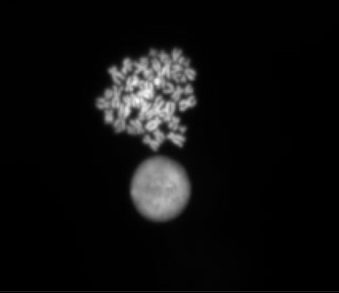

Hypotonic Soutions

Use of different hypotonics on a 47,XY, +21 lymphoblastoid cell line

courtesy of Ping Jin, Dr Jules Clyde and Helen Picton.

Dept Obstetrics and Gynaecology, University of Leeds

Potassium Chloride Solution